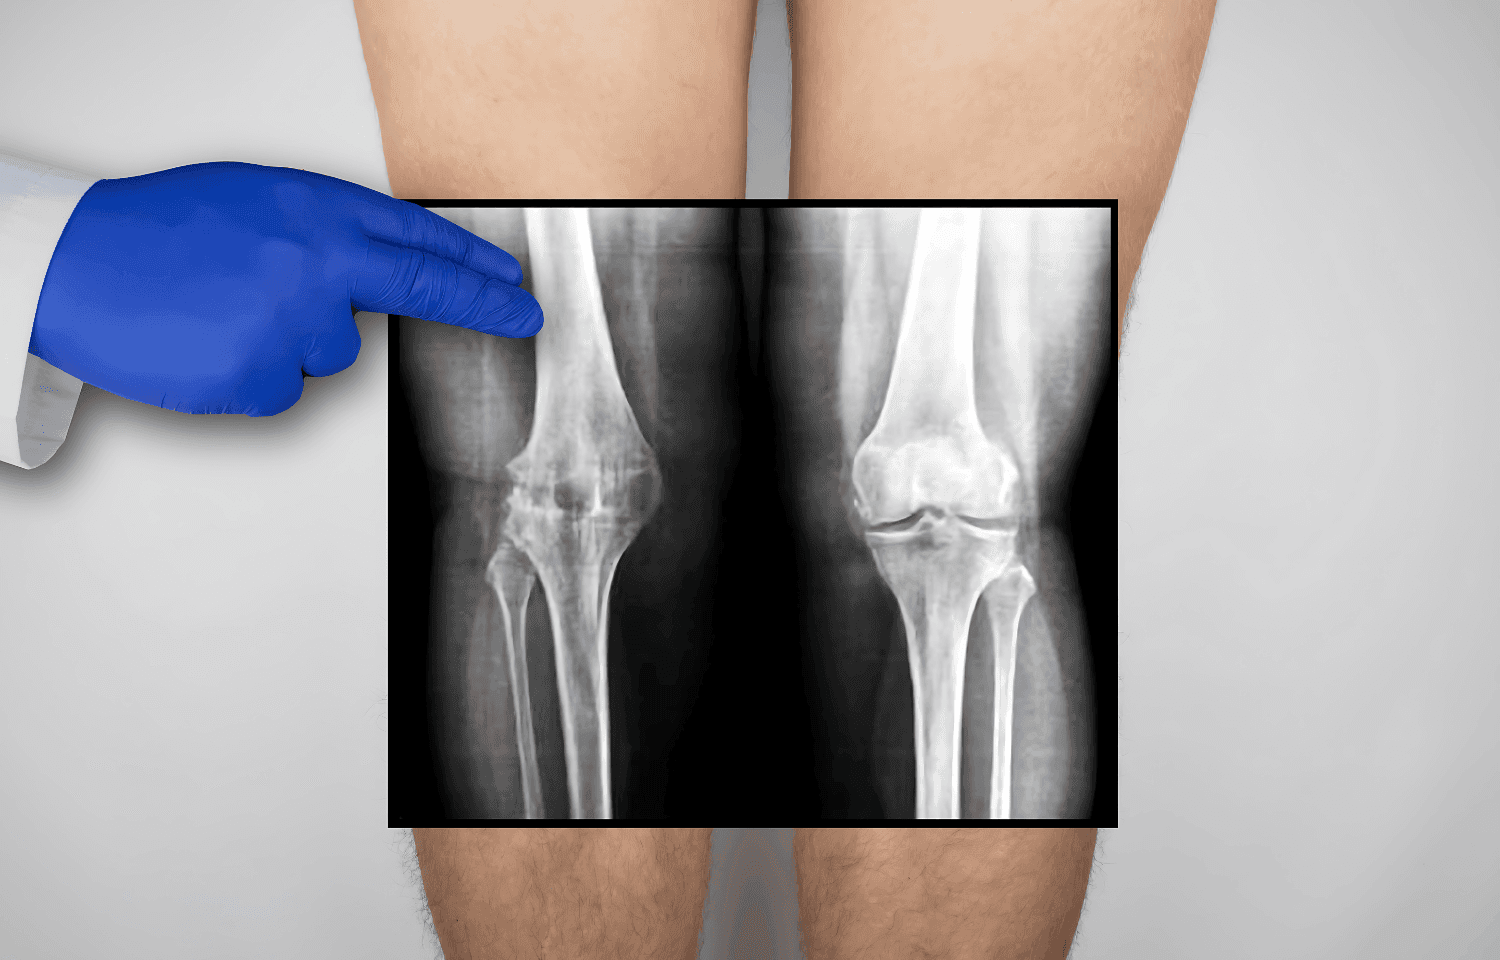

Röntgen görüntüleri, kemik ve eklem yapılarının detaylı incelenmesini sağlayarak bu süreçte kritik bir rol oynar. Röntgen, basit ve hızlı uygulanabilir bir görüntüleme yöntemi olarak birçok alanda değerlendirilir.

Röntgen Kullanım Alanları:

- Kırık ve çatlakların teşhisi

- Eklem sorunlarının tanımlanması

- Karmaşık yaralanmaların analizi

Röntgen görüntülerinin doğru okunması, tedavi planlamasında hataları en aza indirir ve uygun cerrahi veya konservatif tedavi yöntemlerinin belirlenmesini sağlar.